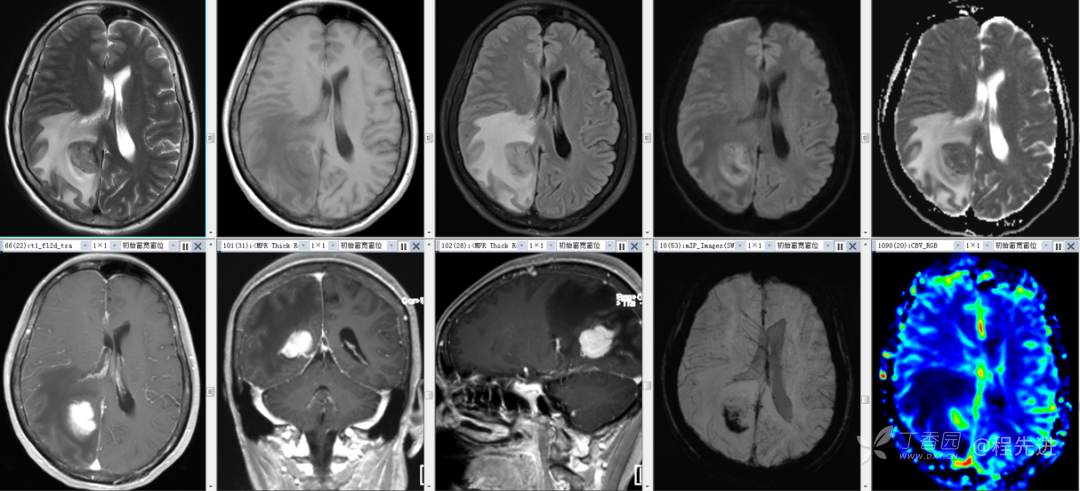

辅助检查:外院头颅 CT 示:右侧顶枕叶占位。

颅脑 MRI 平扫+增强: